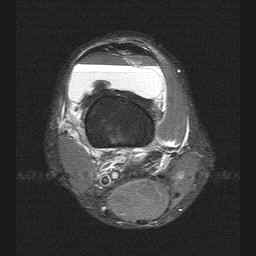

Image 3: Axial STIR image demonstrating the supression of fat (superior layer) on this sequence with bright serum layering on dependant cellular components of blood. CLICK TO ENLARGE.

CLICK TO ENLARGE